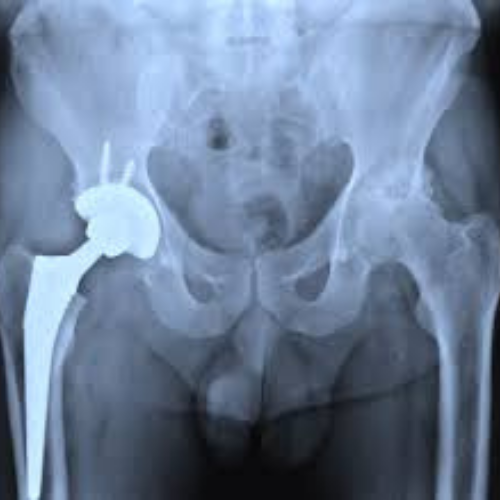

Dr. Nishant Bhatia performs:

• Hip Pinning (Internal Fixation)

• Hemiarthroplasty (Partial Hip Replacement)

• Total Hip Replacement

• Fracture Stabilization with Plates and Screws